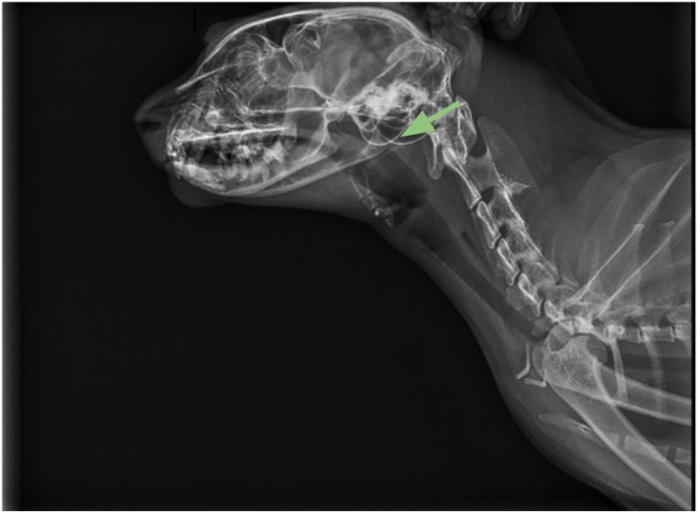

Las radiografías de cráneo pueden ser sugerentes de estenosis nasofaríngea, observándose opacidad de tejido blando dentro de la nasofaringe dorsal, y con frecuencia una desviación dorsal o deformación del paladar blando en el sitio de la estenosis4.

Ante la sospecha de una alteración de vías altas compatible con estenosis o pólipo nasofaríngeo, se realizó una radiografía de cráneo, en la cual se mostraba una alteración en la región nasofaríngea, a la altura de la zona de proyección de las coanas (Figura 2-3), compatible con una estenosis nasofaríngea o imperforación nasofaríngea.

En la radiografía de cráneo, se observó alteración en la región nasofaríngea, a la altura de la zona de proyección de las coanas, compatible con una estenosis o imperforación nasofaríngea.